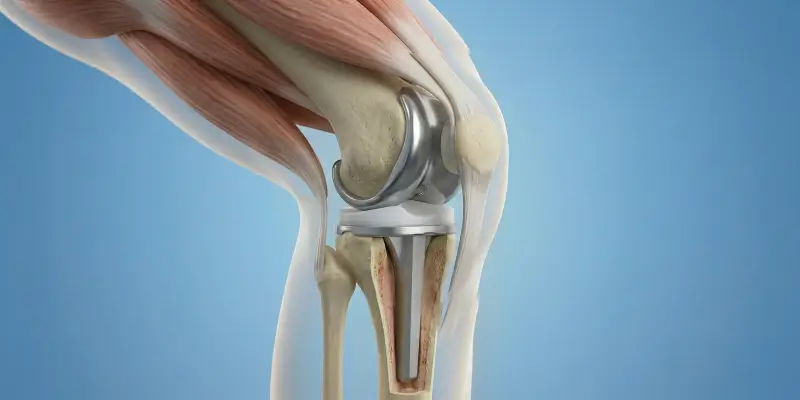

Total diz protezi, ileri osteoartrit ve diz hasarında hasarlı kıkırdak ve kemik yüzeylerinin metal ve polietilen protezle değiştirilmesidir. Endikasyonlar, cerrahi ve rehabilitasyon.

Revizyon cerrahisi, kalça veya diz protezinin gevşeme, aşınma, enfeksiyon veya instabilite nedeniyle yenilenmesidir. Endikasyonlar, süreç ve rehabilitasyon.

Robotik diz ve kalça protezi, 3D görüntüleme ve robotik rehberlik ile hassas, kişiye özel protez yerleştirmesidir. Avantajlar, endikasyonlar ve rehabilitasyon.